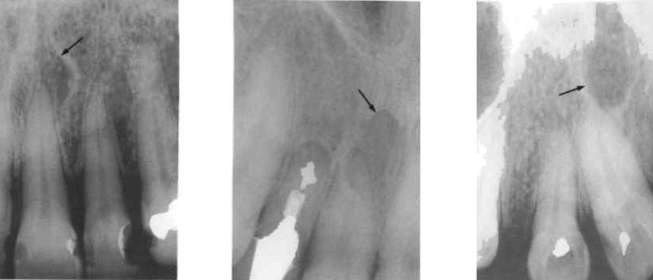

periapical radiolucencies

around the tip of the tooth root

important in endodontic diagnosis

most common radiolucency in the jaws

usually caused by pulpal (nerve) disease

recent lesions in periapical:

no radiopaque border

grow faster

long-standing lesions in periapical:

surrounded by a radiopaque (white) line

grow slowly

—radiographs cannot confirm if a lesion is a cyst

very early periapical changes

some early changes can be reversible

pulp vitality may still be maintained

seen in cancellous bone around the root apex

changes include:

altered trabecular bone pattern

slight increase in radiopacity

periodontal ligament (PDL) changes

widened PDL space is an early sign of disease

can be seen:

around the root apex

in the furcation area

often linked to pulpal pathology

lateral radiolucencies

not associated with the apex

occur along the side of the root

commonly caused by lateral canals

can appear even after endodontic treatment